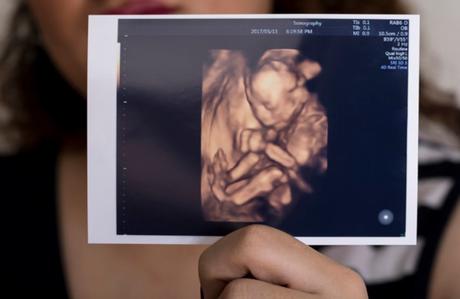

Las ecografías 4d y 5d nos muestran por primera vez a nuestro bebé. Es un momento grande, totalmente emocionante ¿verdad?

Aunque fijaros, no está tan mal que se esconda, porque gracias a eso aparecen imágenes tan curiosas e inolvidables como esta:

En una ecografía 4d conseguirás ver la carita de tu bebé, no pienses en una foto en primer plano, es complicado, porque los bebés están dobladitos, pero también puede conseguirse. Podrás ver como tu bebé bosteza, se coge los pies, abre y cierra las manos, agarra el cordón umbilical, duerme, saca la lengua… Hace siglos ver al bebé así hubiera sido “brujería” pero ahora es un capricho que todas las mamás podemos permitirnos, porque no es caro.